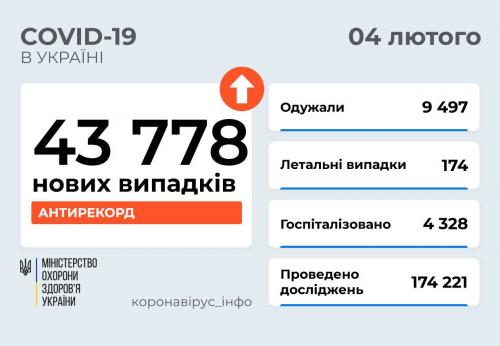

МОЗ: Уперше з початку пандемії було зроблено понад 100 тисяч ПЛР-досліджень за добу

03.02.2022 12:10